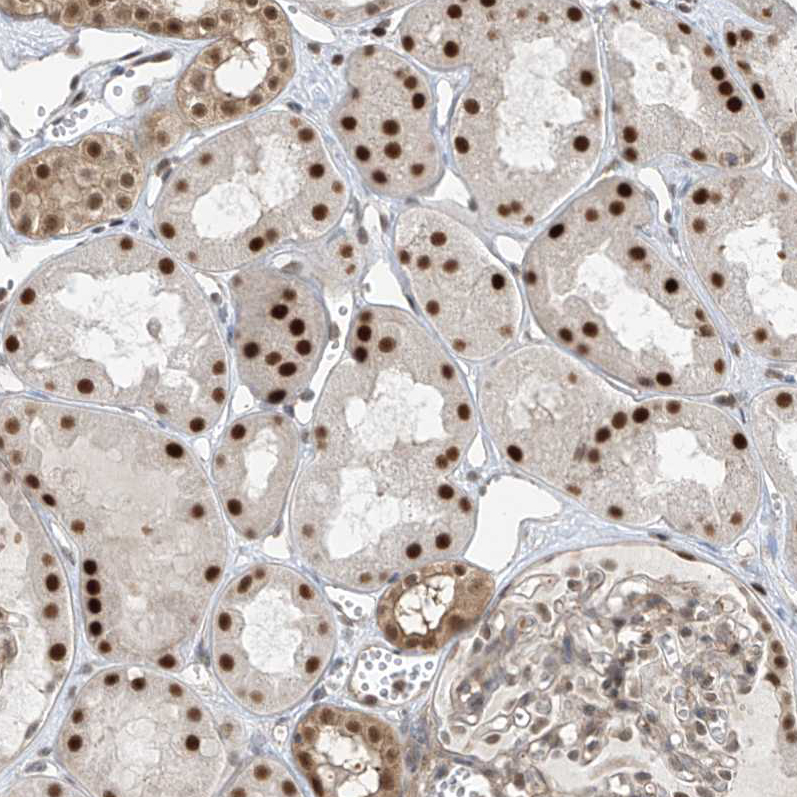

Immunohistochemical staining of human pancreas shows strong nuclear positivity in exocrine glandular cells.